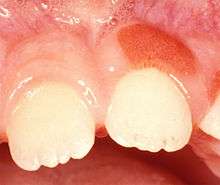

| Plasma cell gingivitis in an adult (histologically verified). | |

Plasma cell gingivitis[1][2] is a rare condition,[3] appearing as generalized erythema (redness) and edema (swelling) of the attached gingiva, occasionally accompanied by cheilitis (lip swelling) or glossitis (tongue swelling).[4] It is called plasma cell gingivitis where the gingiva (gums) are involved,[5] plasma cell cheilitis,[5] where the lips are involved, and other terms such as plasma cell orifacial mucositis,[5] or plasma cell gingivostomatitis where several sites in the mouth are involved. On the lips, the condition appears as sharply outlined, infiltrated, dark red plaque with a lacquer-like glazing of the surface of the involved oral area.[5]

Plasma cell gingivitis appears as mild gingival enlargement and may extend from the free marginal gingiva on to the attached gingiva.[8] Sometimes it is blended with a marginal, plaque induced gingivitis, or it does not involve the free marginal gingiva. It may also be found as a solitude red area within the attached gingiva (pictures). In some cases the healing of a plaque-induced gingivitis or a periodontitis resolves a plasma cell gingivitis situated a few mm from the earlier plack-infected marginal gingiva. In case of one or few solitary areas of plasma cell gingivitis, no symptoms are reported from the patient. Most often solitary entities are therefore found by the dentist.[2]

The gums are red, friable, or sometimes granular, and sometimes bleed easily if traumaticed.[8] The normal stippling is lost.[7] There is not usually any loss of periodontal attachment.[8] In a few cases a sore mouth can develop, and if so pain is sometimes made worse by toothpastes, or hot or spicy food.[7] The lesions can extend to involve the palate.[7]